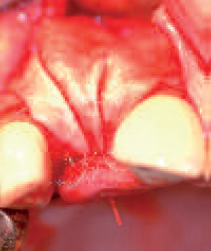

Presentation of three-dimensional bone defect from occlusal view

Presentation of three-dimensional bone defect from occlusal view

Bone

grafts fixed with micro-screws

Presentation of three-dimensional bone defect from occlusal view

Autologous bone material positioned on top of the defect; collagen membrane palatally fixed with suture